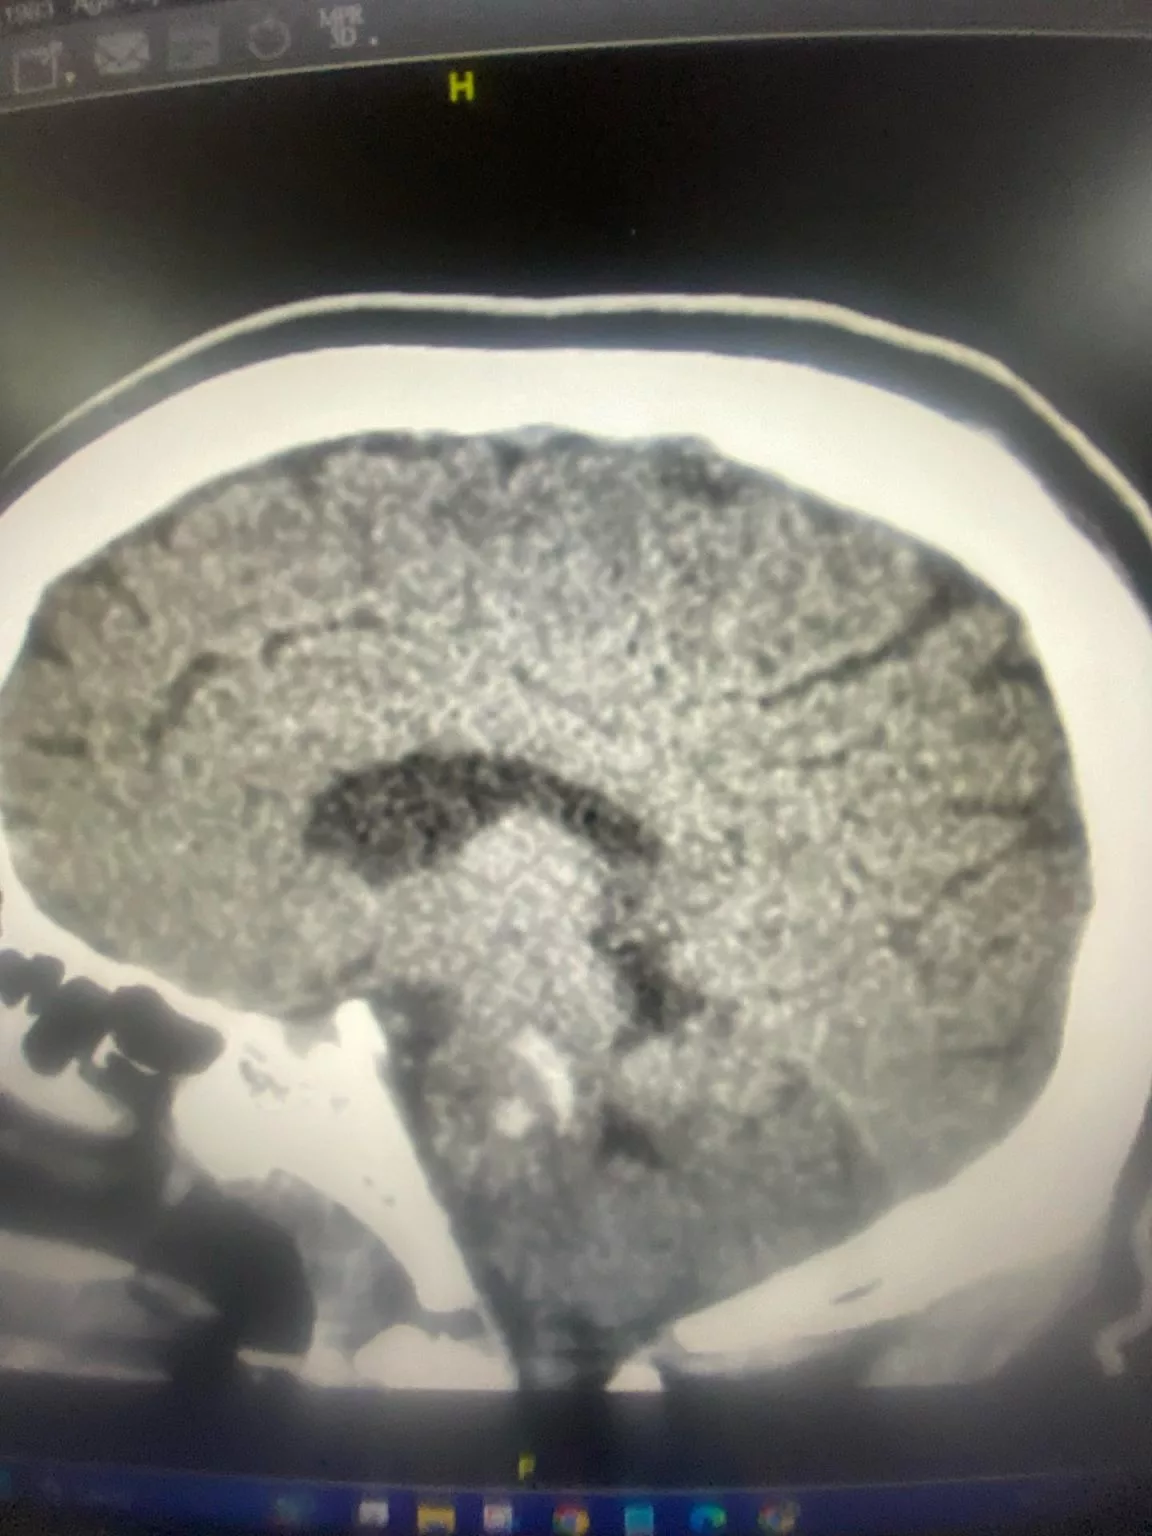

Dalam hantaran tersebut, beliau melaporkan semakin banyak kes melibatkan pesakit berusia antara 30 hingga 40 tahun yang mengalami komplikasi serius seperti pendarahan otak. Antaranya termasuk seorang pesakit lelaki berumur 41 tahun yang dimasukkan ke jabatan kecemasan akibat pendarahan kepala yang berpunca daripada tekanan darah tinggi tidak terkawal.